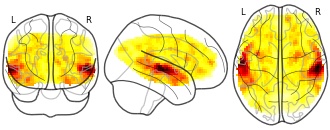

License information was derived automaticallyDescriptionReal value multi-values defined by non-directional analysis.

Multivoxel pattern analysis (MVPA) has gained enormous popularity in the neuroimaging community over the past few years. At the group level, most MVPA studies adopt an “information based” approach in which the sign of the effect of individual subjects is discarded and a non-directional summary statistic is carried over to the second level. This is in contrast to a directional “activation based” approach typical in univariate group level analysis, in which both signal magnitude and sign are taken into account. The transition from examining effects in one voxel at a time vs. several voxels (univariate vs. multivariate) has thus tacitly entailed a transition from directional to non-directional signal definition at the group level. While a directional group-level MVPA approach implies that individuals have similar multivariate spatial patterns of activity, in a non-directional approach each individual may have a distinct spatial pattern. Using an experimental dataset, we show that directional and non-directional group-level MVPA approaches uncover distinct brain regions with only partial overlap. We propose a method to quantify the degree of spatial similarity in activation patterns over subjects. Applied to an auditory task, we find higher values in auditory regions compared to control regions.